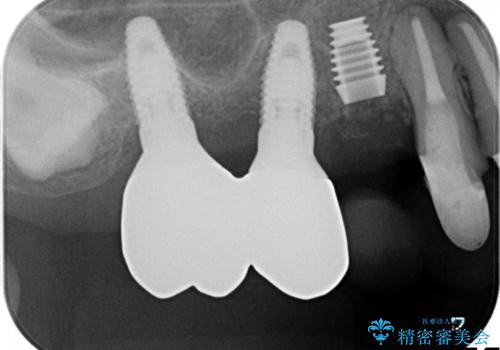

薄い骨にもインプラントを スプリットクレスト+ショートインプラントの応用

- 破折により保存不可能となった歯を抜歯後、待時してインプラントを計画した。

骨が薄く、インプラントの径に耐え得ないと判断したためスプリットクレストにより骨幅を拡大しインプラントを埋入した。

スプリットクレストやリッジエキスパンジョンといった方法は、骨が薄く、細い場合に、割線を設定し、狭い骨幅を拡大すると同時にインプラントを埋入することができます。

インプラントの種類:Bicon

かぶせ物の種類:PFZ